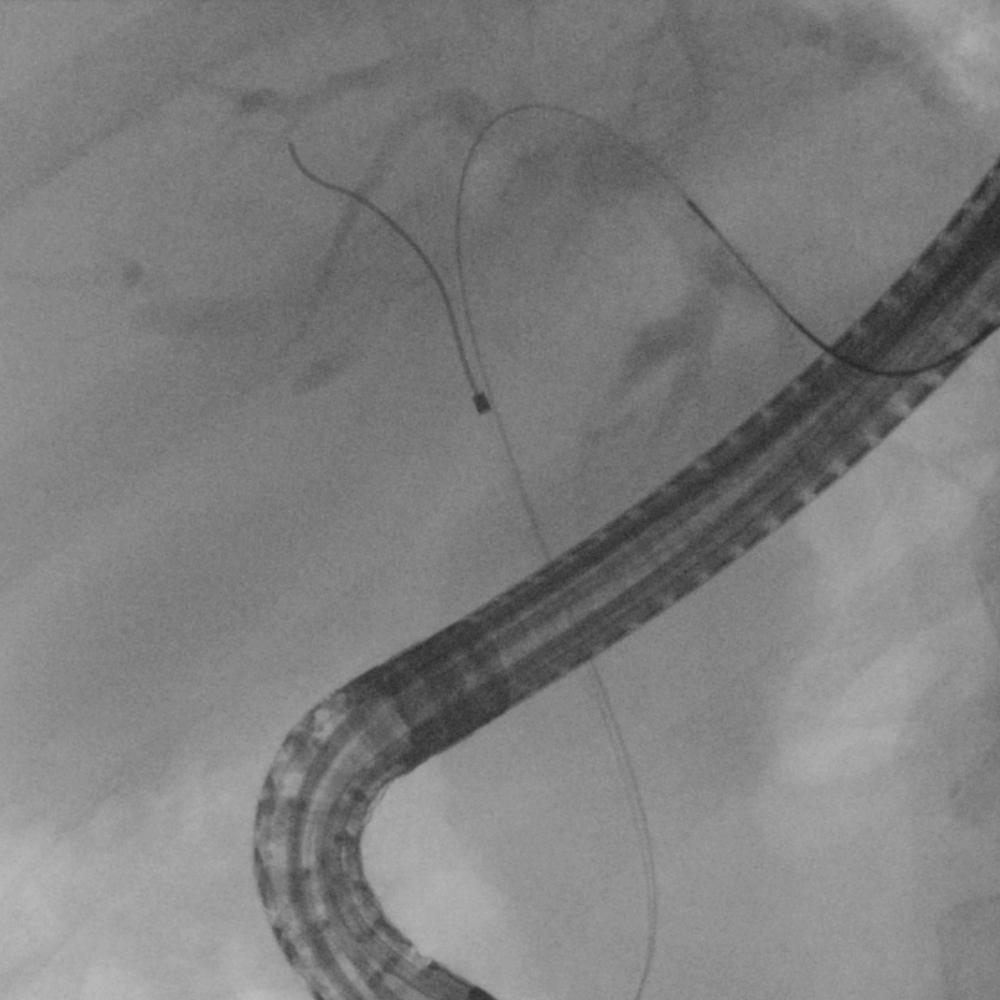

1. Targeted cannulation of a single enlarged segmental branch in the left lobe of the liver in cases of liver metastases.

Case 1